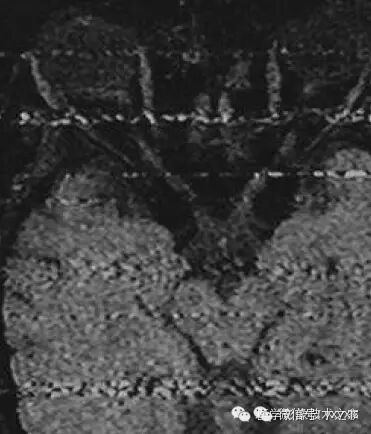

细线伪影 (fine line artifact)

原因:

来源于射频脉冲的受激回波对图像采集的第一个回波产生干扰。

图像特点:

伪影较细小,出现在图像的局部,可能比较模糊,甚至需要在特殊窗宽窗位下才能发现。